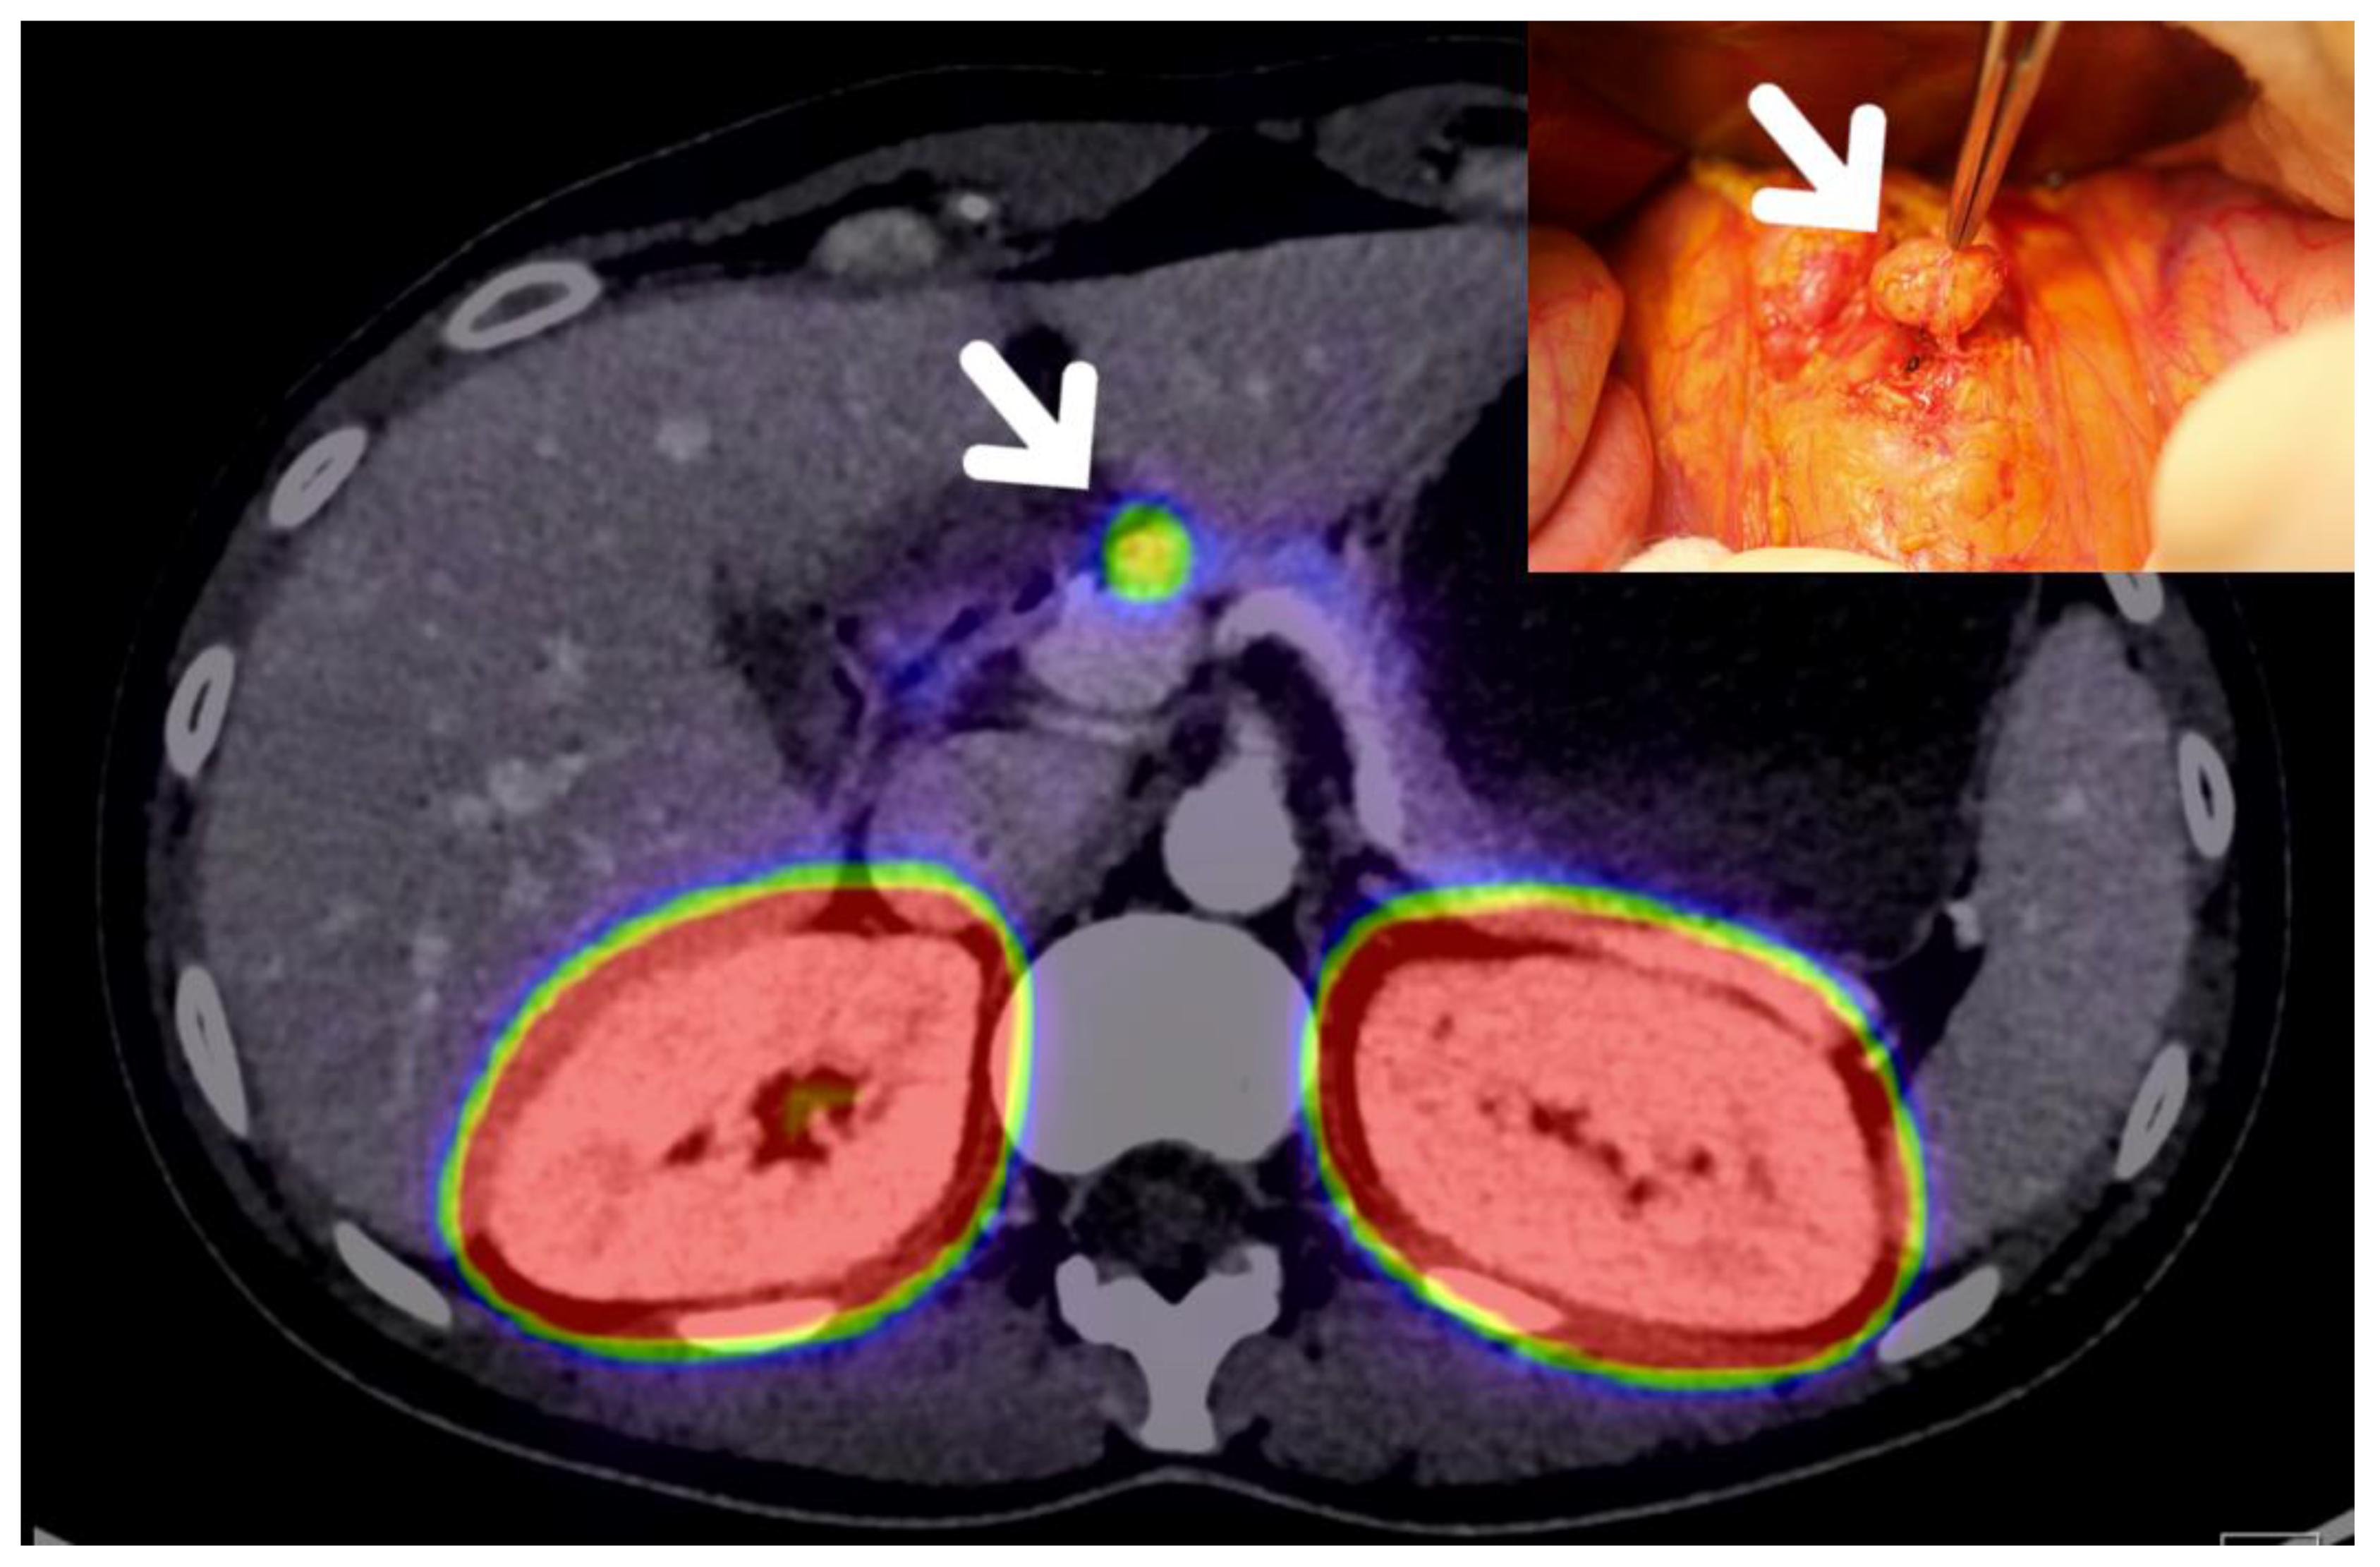

- Tierney, J.F.; Kosche, C.; Schadde, E.; Ali, A.; Virmani, S.; Pappas, S.G.; Poirier, J.; Keutgen, X.M. (68)Gallium-DOTATATE positron emission tomography-computed tomography (PET CT) changes management in a majority of patients with neuroendocrine tumors. Surgery 2019, 165, 178–185. [Google Scholar] [CrossRef]